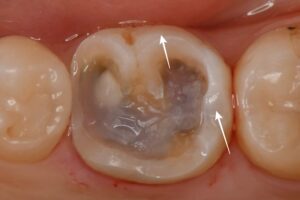

他院で定期検診をされていた方です。痛みが続くため相談されたそうですが、何もないとのことで毎回診察が終わっていたそうです。

当院にてレントゲン写真を行ったところ、昔治した歯の神経が不可逆性の歯髄炎を起こしていたため、歯内療法専門医と連携し根管治療、その後痛みがなくなったことを確認してからジルコニアの被せ物を行なった。

| 精密根管治療後、ジルコニアセラミックで治療(30代女性) |

| 前の歯医者でなんともないと言われたが痛みが止まらない |

| 精密根管治療後、セラミックによる被せ物を2本同時に行なった |